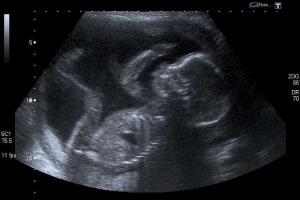

Rep. Terri Collins (R-Decatur), sponsor of the House bill, said the bill passed Thursday is designed to 'confront a decision that was made by the courts in 1973 that said the baby in a womb is not a person,' Collins added. "This bill addresses that one issue. Is that baby in the womb a person? I believe our law says it is.'

'It is meant to actually use some of the same language that is addressed in Roe vs. Wade. So, hopefully it just completely takes it all the way to the Supreme Court eventually to overturn.'